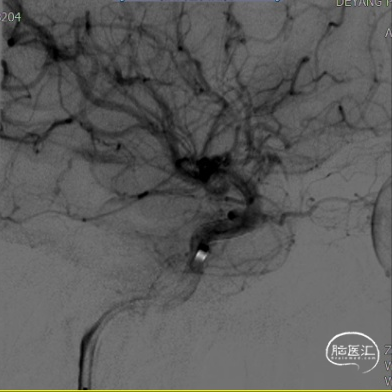

(A)

(B)

(C)

(D)

(E)

(F)

A:准备定位后打开Surpass Streamline头端于Catalyst 5。

B:缓慢回撤Catalyst 5,逐渐释放Surpass Streamline。

C:支架收尾。

D:Catalyst 5中间导管进行支架内按摩。

E:动脉瘤腔内可见造影剂滞留。

F:动脉瘤腔内可见造影剂滞留(另一角度)。